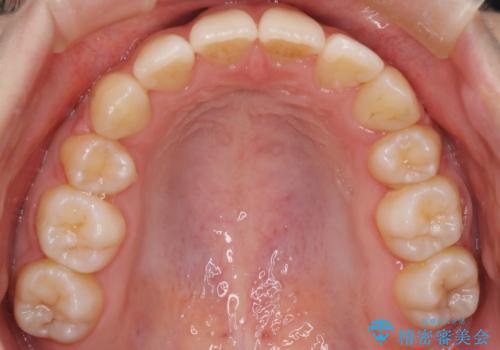

ワイヤーによる抜歯矯正でガタガタの改善

- 前歯のがたがたを主訴に来院されました。

上下の前歯が前方に傾斜しているのもあり、内側に前歯をひっこめるために上下左右の歯を1本ずつ抜歯して矯正することとしました。

ガタガタも改善しましたが、前歯が内側に引っ込むことにより口元もすっきりして、唇が閉じやすくなりました。